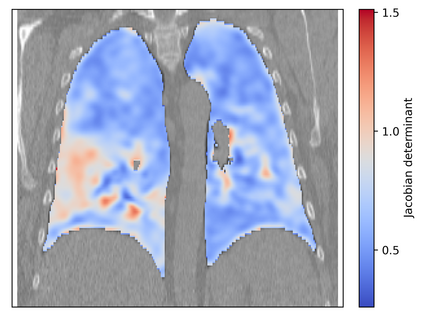

Deformable image registration is a fundamental task in medical image analysis and plays a crucial role in a wide range of clinical applications. Recently, deep learning-based approaches have been widely studied for deformable medical image registration and achieved promising results. However, existing deep learning image registration techniques do not theoretically guarantee topology-preserving transformations. This is a key property to preserve anatomical structures and achieve plausible transformations that can be used in real clinical settings. We propose a novel framework for deformable image registration. Firstly, we introduce a novel regulariser based on conformal-invariant properties in a nonlinear elasticity setting. Our regulariser enforces the deformation field to be smooth, invertible and orientation-preserving. More importantly, we strictly guarantee topology preservation yielding to a clinical meaningful registration. Secondly, we boost the performance of our regulariser through coordinate MLPs, where one can view the to-be-registered images as continuously differentiable entities. We demonstrate, through numerical and visual experiments, that our framework is able to outperform current techniques for image registration.